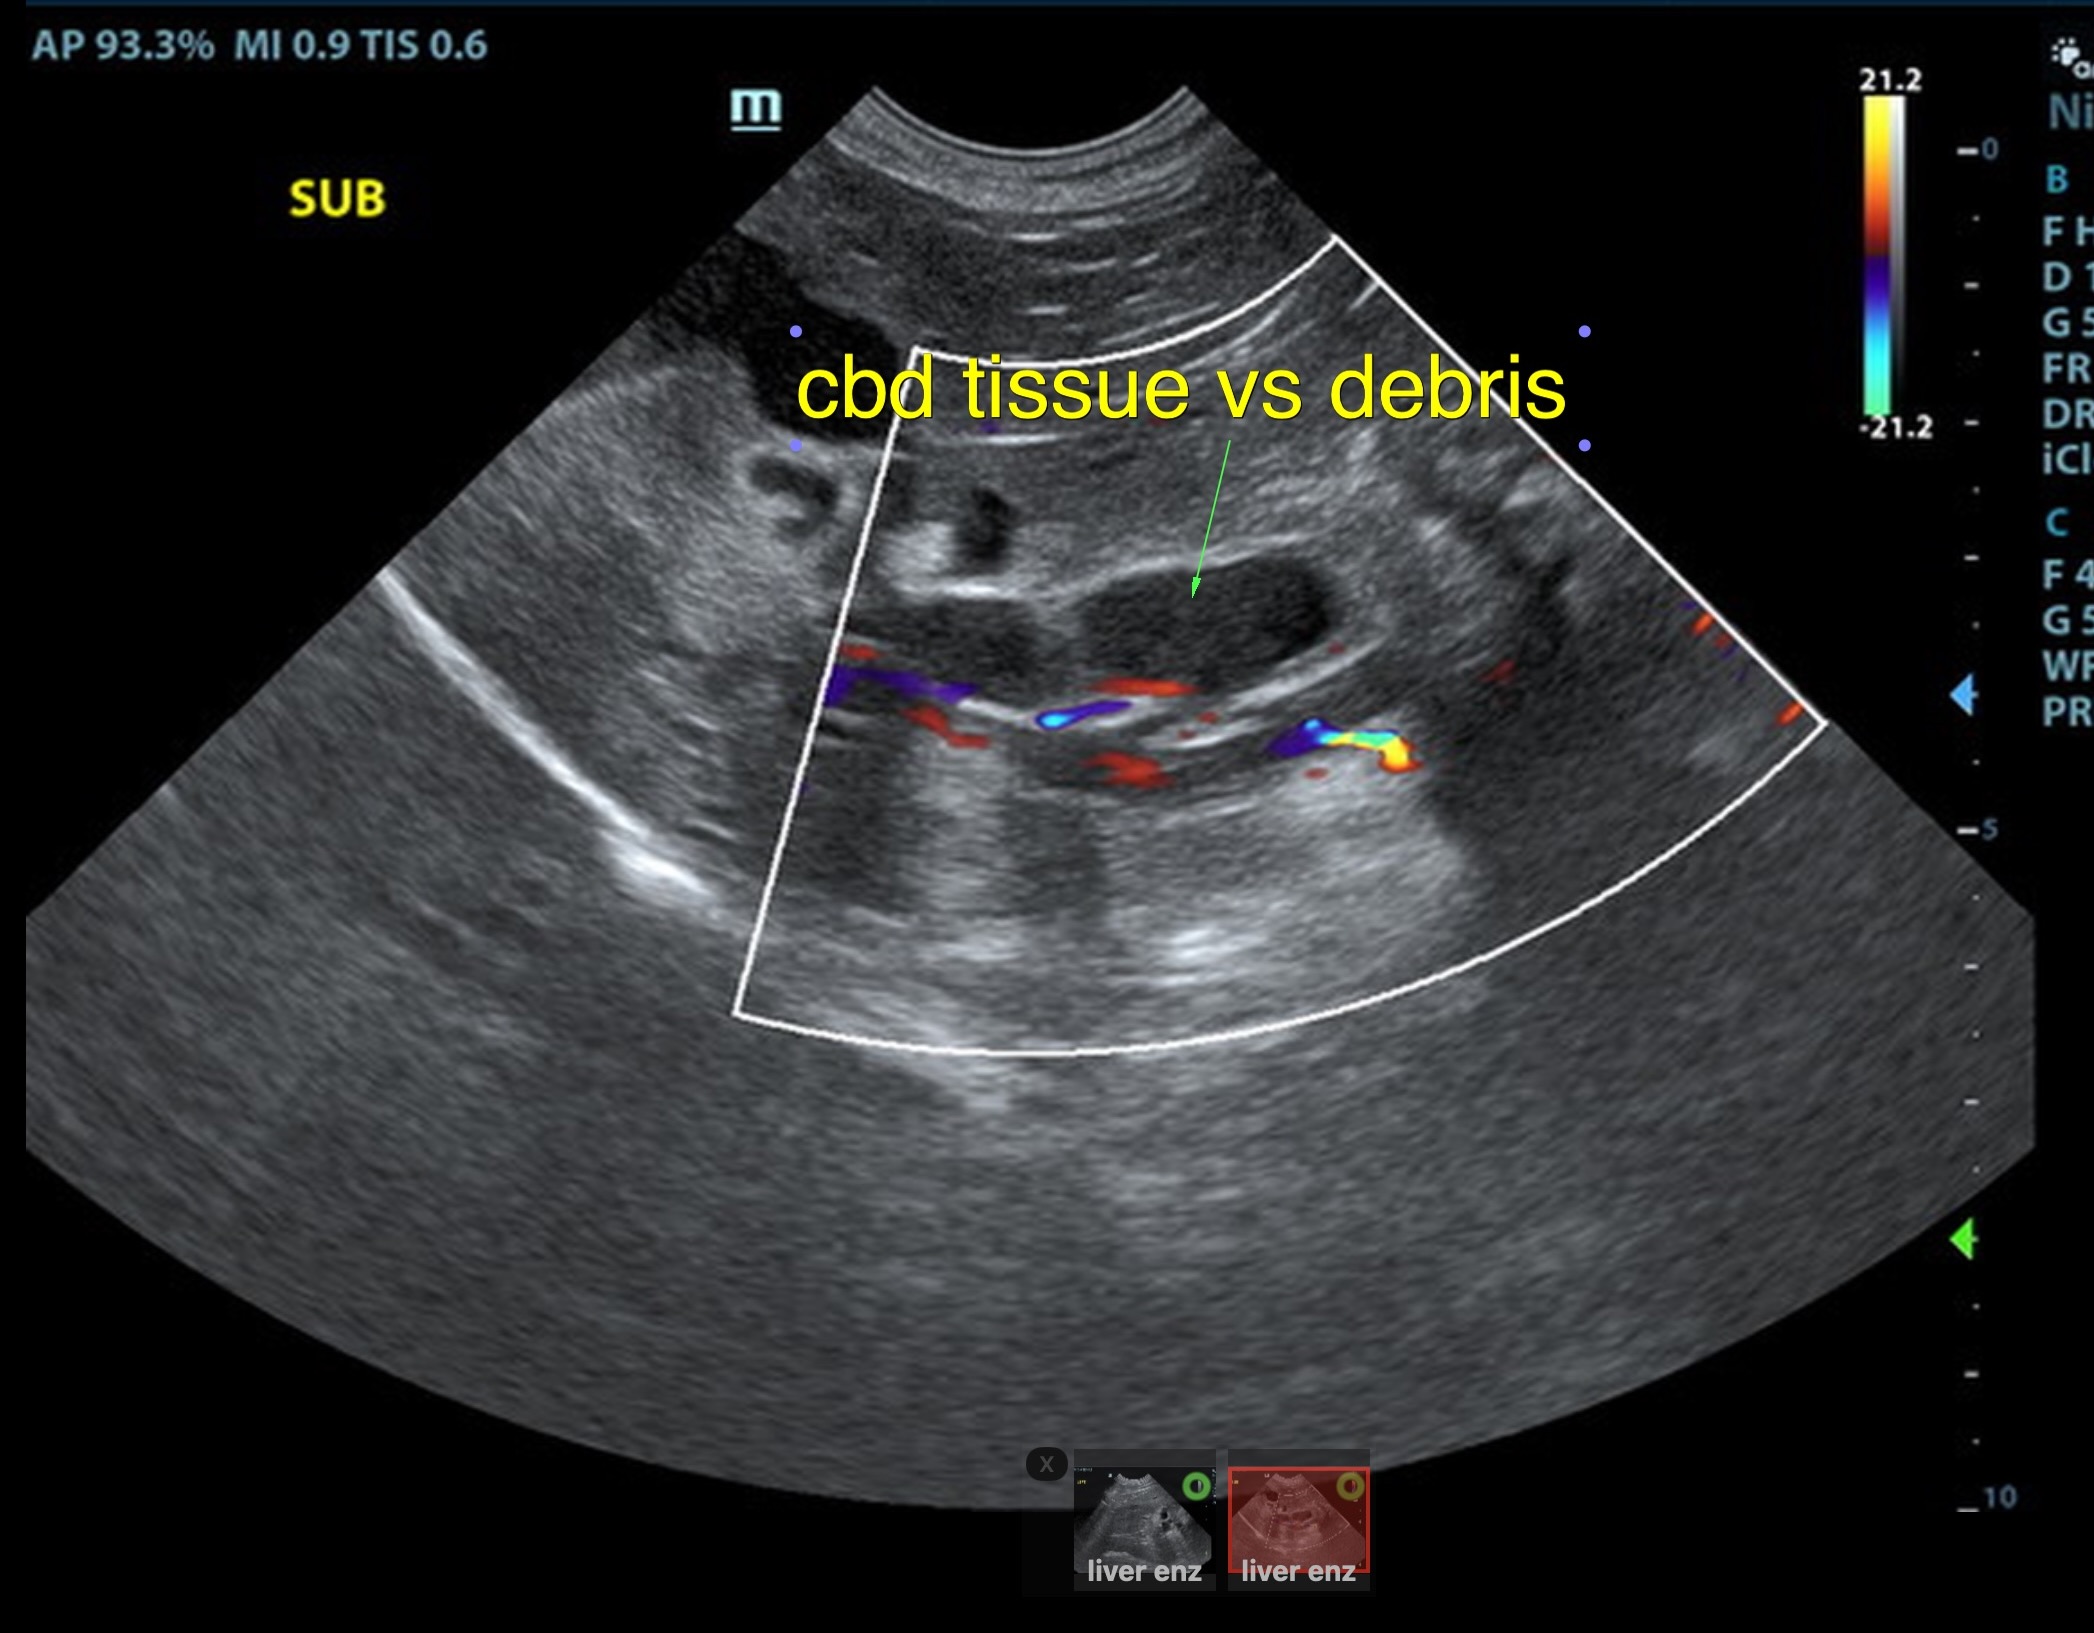

Local biliary duct dilation noted with post hepatic obstruction. Gallbladder was turgid. The common bile duct (CBD) was dilated with echogenic debris or possible tissue proliferation. The CBD measred 0.86 cm. An overt mass was noted at the common bile duct termination, measuring 2.0 cm. Target-type nodules noted in the liver.